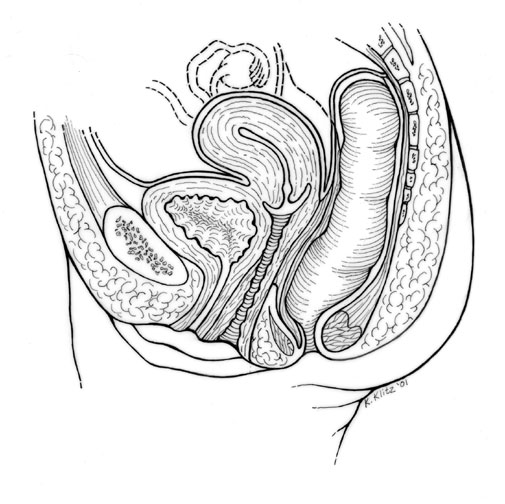

Female Pelvis Drawing |